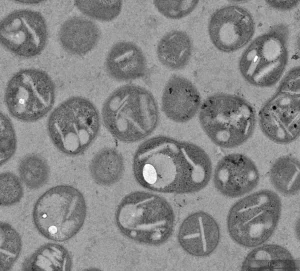

Leer másLa Fundación Reina Sofía, el CSIC y la Fundación Primafrio, colaboran en la investigación de vanguardia en Biotecnología para la gestión sostenible de plásticos